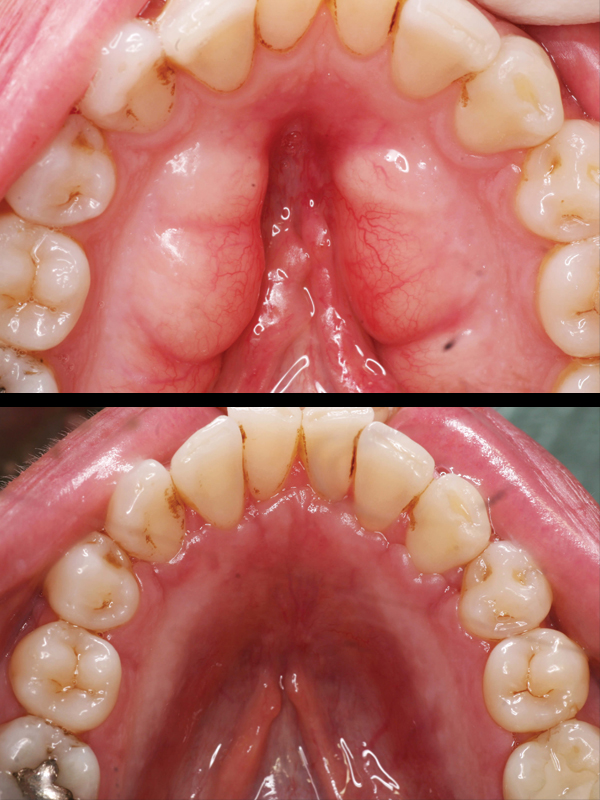

Periodontal Tooth Movement (Limited Orthodontics):

Bone loss (as a result of periodontal disease) can cause your teeth to shift. Shifting teeth can be unsightly, difficult to chew with, loose, harder to clean, and sometimes harder to restore.

Some of these situations are easily corrected with periodontal tooth movement i.e. minor orthodontics. Treatment time can take as little as 3-6 months and provide both you and your doctor with a healthy and cosmetic foundation from which to complete your restorative care.

Dr. Sterrett received comprehensive training in his graduate program on this type of therapy and he would be glad to share with you his thoughts about your case and answer any questions you may have.